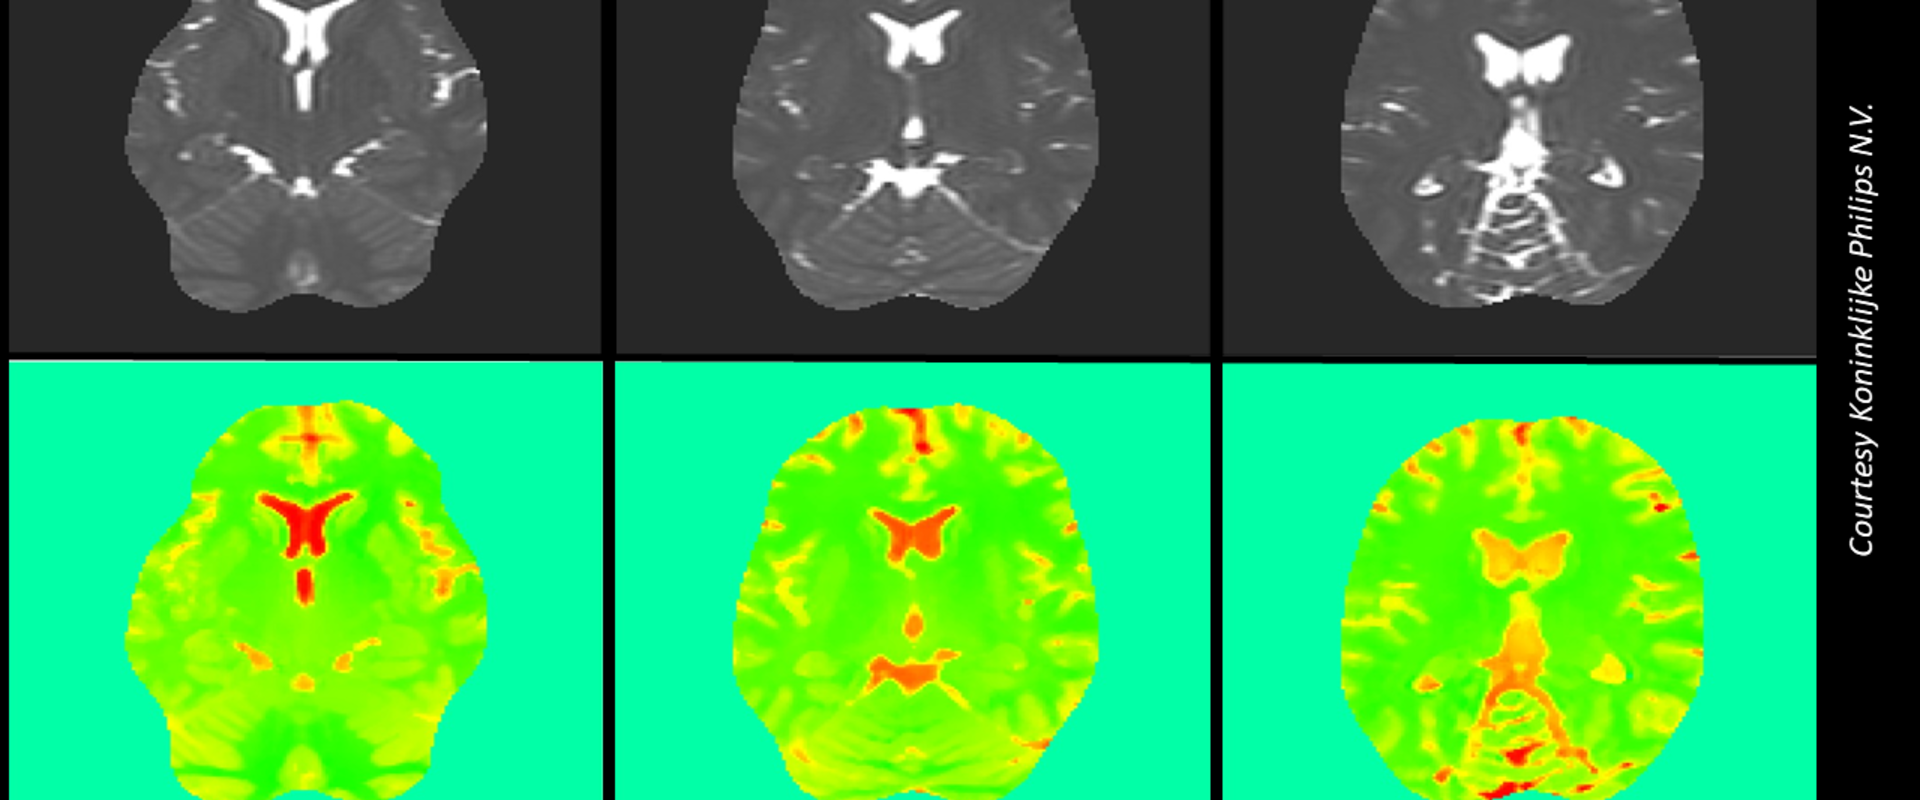

Electric Properties Tomography (EPT) is a MR-based method that does not require contrasting agents. Different body tissues have different electrical conductivities that interact with the scanners’ radiofrequency magnetic field, causing fluctuations that can be interpreted to provide quantitative data.

During the EMUE project, the first MU assessment for the commonly used Helmholtz-EPT technique was performed. To avoid the uncertainty arising from different tissue types, a homogenous phantom was constructed containing salt water to mimic the average electrical conductivity of the human body. Twenty-five scans were performed with the phantom stationary in a Philips 3 T Ingenia TX MRI instrument to provide repeatability measurements without the uncertainty due to placement. The analysis allowed accounting for many sources of uncertainty, such as the measurement fluctuations of the MR signal and imaging artefacts.

Measurement uncertainty was propagated through the mathematical model implemented in EPTlib, open-source software developed in the context of QUIERO, a project developing metrology for quantitative MRI. A major factor affecting the uncertainty propagation was the choice of kernel used, which defines the mathematical ‘smoothing’ applied to the voxels (the 3D representation of the pixels in scan images) during image processing.

The study revealed that the repeatability uncertainty was very small - indicating good repeatability for this technique. However, spatial fluctuations were observed in the obtained conductivity images, indicating the need of a more extended uncertainty assessment. To this end, a further set of scans of the phantom at different positions were performed in the QUIERO project to assess the MU associated with reproducibility. The resulting reproducibility uncertainty was in good agreement with the observed spatial fluctuations of each single scan.